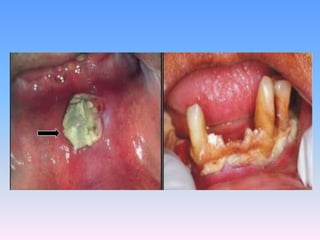

Begins as a small ulcer of the gingival mucosa which

rapidly spreads and involves the surrounding tissues of

jaw, lips and cheeks by gangrenous necrosis.

The overlying skin becomes inflamed ,edematous , and

finally Necrotic,With the result that a line of

demarcation develop between healthy and dead

tissues, and large mass of tissues may slough

out,leaving the jaw exposed.

Gangrene is denoted by appearance of blackening of

the skin .

Subcutaneous fat pad and buccal fat pad undergo

necrosis in advance of other adjoining tissues.